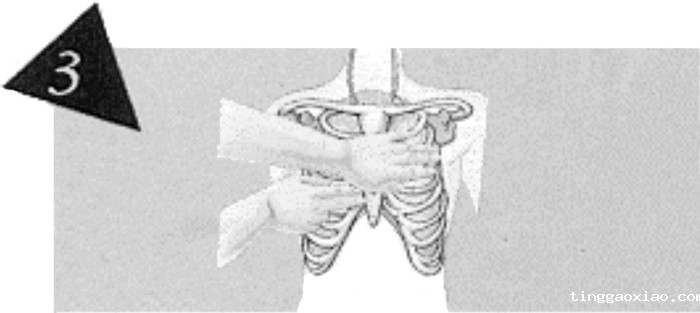

掌根放好位置后,另一手重叠于其上。

将两手的手指互扣或跷起,以免压迫肋骨造成骨折。

有关节炎者为他人实行胸外按压时,施救者依照图一、二、三的做法,一手掌根放好位置后,以另一手紧握此手的手腕部。